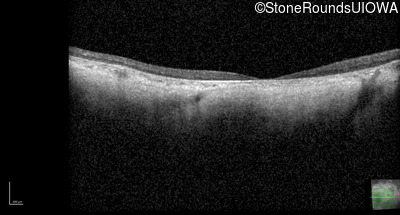

Optical Coherence Tomography - Right - 10/200 -2 sc

Exemplar / OCT Stack